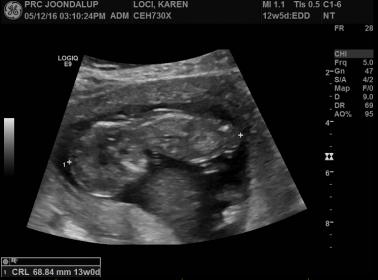

3rd,4th,5th and 6th are 12 week shots